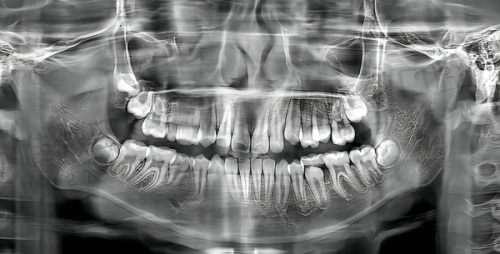

再给大家透个底:思南县人民医院的正畸方案是“个性化定制”的——医生会先用**数字化全景机**拍你的牙齿片,再用电脑模拟矫正后的成效,让你提前看到“整完牙的样子”,而且整个矫正过程都会有医生跟进,有问题随时找得到人,特别放心!